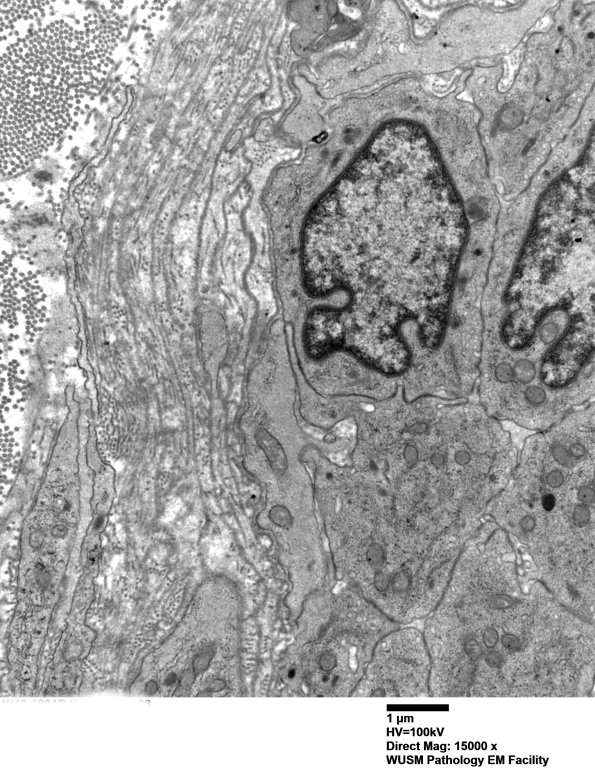

Washington University Experience | VASCULAR | Hypoxia-Ischemia, fetal-neonatal | White Matter | 15B2 (Case 15) HIEM EM 003 - Copy

15B2 (Case 15) HIEM EM 003 - Copy